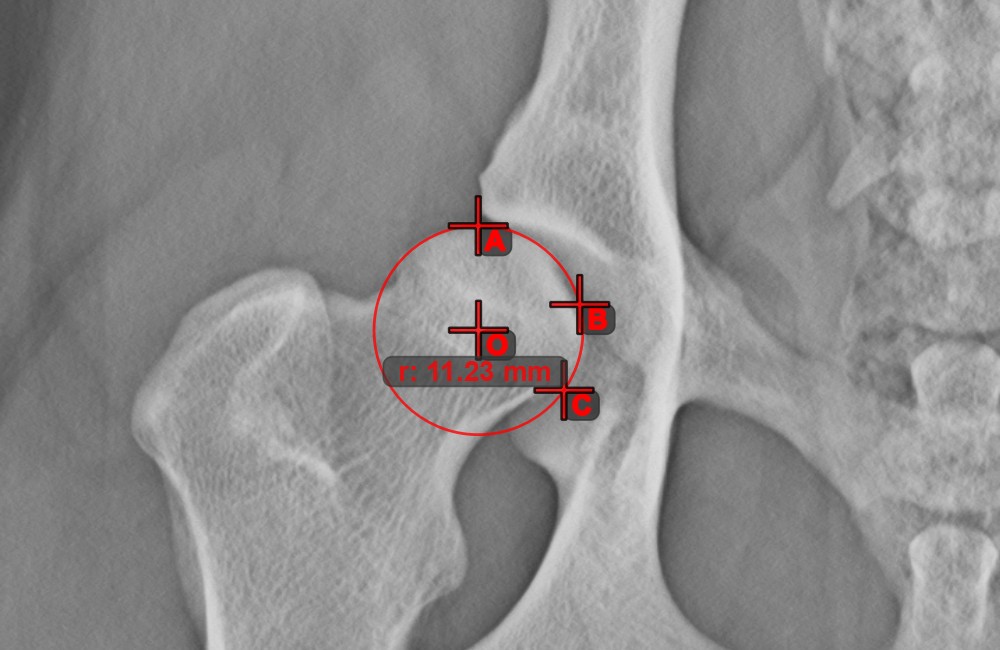

Kör 3 pontból¶

A Kör 3 pontból eszköz egyszerű és hatékony módja annak, hogy mindössze három pont alapján hozzon létre egy tökéletes kört.

Kezdje az eszköz kiválasztásával a bal oldali eszköztárból, és rendelje hozzá az egyik elérhető egérgombhoz. Helyezze el a kör három pontját, vagy válassza ki a pontokat a jelenetben már meglévők közül. A kör automatikusan létrejön a három pont elhelyezkedése alapján. A kör origója mindig O betűvel lesz jelölve. A kör sugara automatikusan kiszámításra kerül.

Módosítsa a három pont helyzetét a kör sugarának megváltoztatásához a Elem kiválasztása/mozgatása eszközzel.